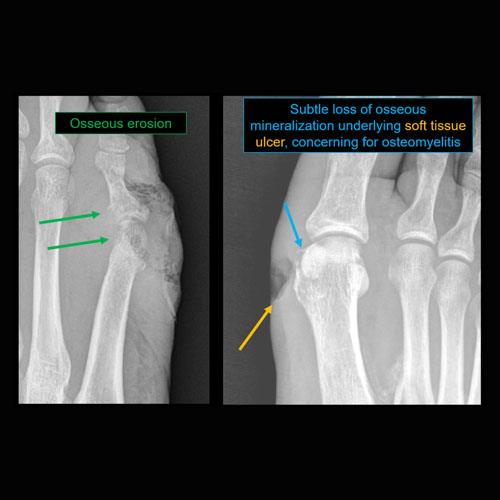

There is soft tissue reticulation, fullness, or obscuration of normal fat planes. |

Yes | NA |

There is soft tissue ulceration. |

There are fractures. |

There is periosteal reaction or osseous destruction suggesting osteomyelitis. |

Soft tissue defect along the medial foot with possible underlying osteomyelitis of the first metatarsal head.

MRI to further evaluate for osteomyelitis.

Urgent (Action Necessary in a few hours)